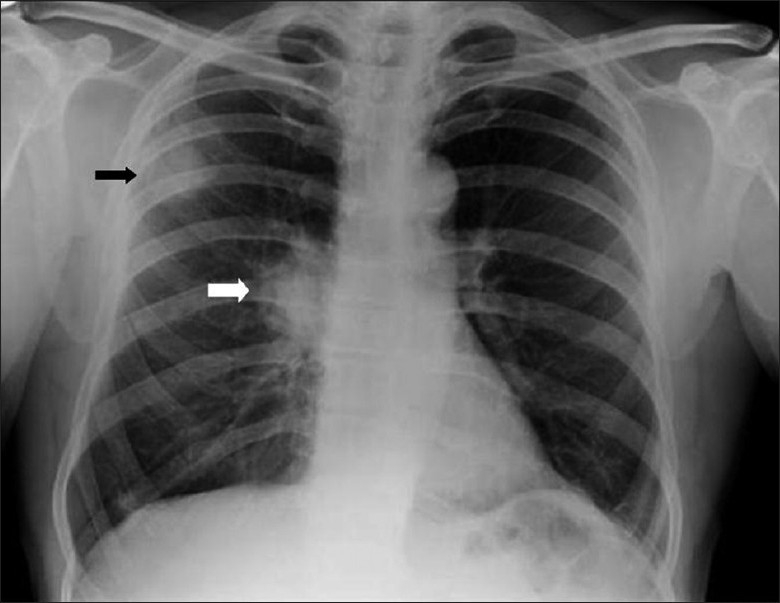

Обследование проводится в прямой (постеро-антериальной) и боковой проекциях грудной клетки, при необходимости дополняется прицельной съёмкой подозрительных зон, рентгеноскопией и томографией для уточнения характеристик образования. Применяются стандартный режим для оценки общей конфигурации лёгочных полей и корней лёгких и высококонтрастный режим для выявления малых очагов, нарушений бронхиальной проходимости и сопутствующих изменений. Рентгенография позволяет выявлять прямые признаки рака бронха, отражающие наличие опухолевого образования, а также косвенные признаки и рентгенологические сигналы, свидетельствующие о вторичных изменениях в лёгочной ткани и средостении.

Плоскоклеточный рак бронха:

Центральное образование в проекции главных или долевых бронхов, часто с неровными или звёздчатыми контурами.

Признаки обструкции бронха: ателектаз соответствующего сегмента или доли лёгкого, с уменьшением объёма и смещением междолевых щелей.

Наличие кавитации внутри опухоли с неровными толстыми стенками — признак распада.

Расширение корня лёгкого за счёт увеличенных лимфатических узлов.

Усиление лёгочного рисунка в зоне дренажа поражённого бронха.

Смещение структур средостения при массивном коллапсе лёгочной ткани.